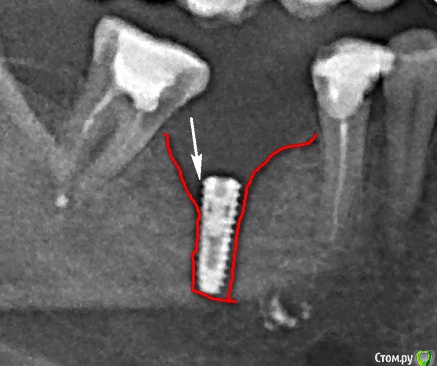

Наталия1966 Опубликовано 1 ноября, 2019 Автор Поделиться Опубликовано 1 ноября, 2019 (изменено) Ну, вот и все. Установлен формирователь. Снимок показал частичное обнажение импланта по передней стенке, задняя покрывает весь имплант. Доктор сказал, что в принципе это допустимо. Если не будет нагноения в передней части импланта, то считайте, что он установлен. Если будет постоянное нагноение, то два варианта - удаление самого импланта, либо попытка подсадки кости на переднюю стенку. Посмотрим, конечно. Я что думаю. Если часть импланта обнажена, то не будет ли зубной камень лепиться к этой части, тело импланта не полировано. Мож отполировать как-то. Тогда прирастет ли десна. Вообщем пока два варианта - удаленье (очень не хотелось бы) и костная пластика. 10-мм имплант утоплен по край сзади и где-то на 5-6 мм спереди. Вот такие пироги! Изменено 1 ноября, 2019 пользователем Наталия1966 Ссылка на комментарий